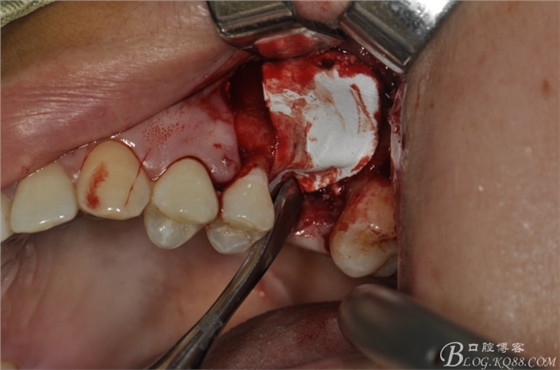

術(shù)中照片。

超聲骨刀切開骨外板 上頜竇外提一例